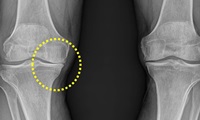

콘드로이친이 부족할 경우 연골은 보수성과 탄력을 잃는다고 합니다. 연골이 계속에서 닳게 되는 경우에는 뼈끼리 마찰이 생겨 부딪히게 되며 관절통이 진행되어 관절염 또한 쉽게 생길 수 있는데요. 콘드로이친 효능 중 가장 잘 알려진 관절통증을 완화시키는 역할을 통하여 얇아서 닳기 쉬운 연골의 마모를 방지해주는 일을하며 관절염의 통증을 개선하는데 도움이 됩니다.

콘드로이친이 연골을 재생시키고 보수성을 높이면서 무릎에 받을 수 있는 충격과 마찰을 흡수시키는 역할을 해 연골을 보호하는일을 하는데요. 실제 연구에서도 4개월간 꾸준히 콘드로이친 1200mg 정도를 섭취한 실험군에게서 관절과 연골의 통증이 43%이상 감소했다는 결과가 있습니다.